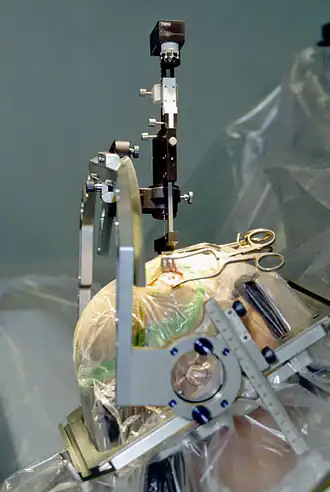

Less than 10% of those with PD qualify as suitable candidates for a surgical response. The three different mechanisms of surgical response for PD are: ablative surgery, (the irreversible burning or freezing of brain tissue), stimulation surgery or deep brain stimulation (DBS), and transplantation or restorative surgery.[22]

Target areas for DBS or lesions include the thalamus, the globus pallidus (the lesion technique being called pallidotomy), or the subthalamic nucleus.[21]

Deep brain stimulation

Deep brain stimulation (DBS) is presently the most used method of surgical treatment because it does not destroy brain tissue, it is reversible, and it can be tailored to individuals at their particular stage of disease. DBS employs three hardware components: a neurostimulator, also called an implanted pulse generator (IPG), which generates electrical impulses used to modulate neural activity, a lead wire which directs the impulses to a number of metallic electrodes towards the tip of the lead near the stimulation target, and an extension wire that connects the lead to the IPG. The IPG, which is battery-powered and encased in titanium, is traditionally implanted under the collarbone, and is connected by the subcutaneous extension to the lead, which extends from outside the skull under the scalp down into the brain to the target of stimulation. The IPG, or the entire three-component system, are sometimes referred to as a brain pacemaker, due to the precedence and renown of cardiac pacemakers and similarities in the components of both types of systems.

The preoperative targeting of proper implantation sites can be accomplished by the indirect and direct methods. The indirect method uses computer tomography, magnetic resonance imaging, or ventriculography to locate the anterior and posterior commissures and then employs predetermined coordinates and distances from the intercommissural line to define the target area. Subsequent histologically defined atlas maps can also be used to verify the target area. The direct method provides visualization and targeting of deep nuclei by applying stereotactic preoperative MRI, which unlike the indirect method, takes into account the anatomic variation of the nuclei's size, position, and functional segregation amongst individuals.[23]

Electrophysial functional mapping, a tool used in both methods to verify the target nuclei, has come under scrutiny due to its associated risks of hemorrhages, dysarthria or tetanic contractions. Recently, susceptibility-weighted imaging, a type of MRI, has shown incredible power in its ability to distinguish these deep brain nuclei and is being used in DBS to reduce the overuse of EFM.[24]